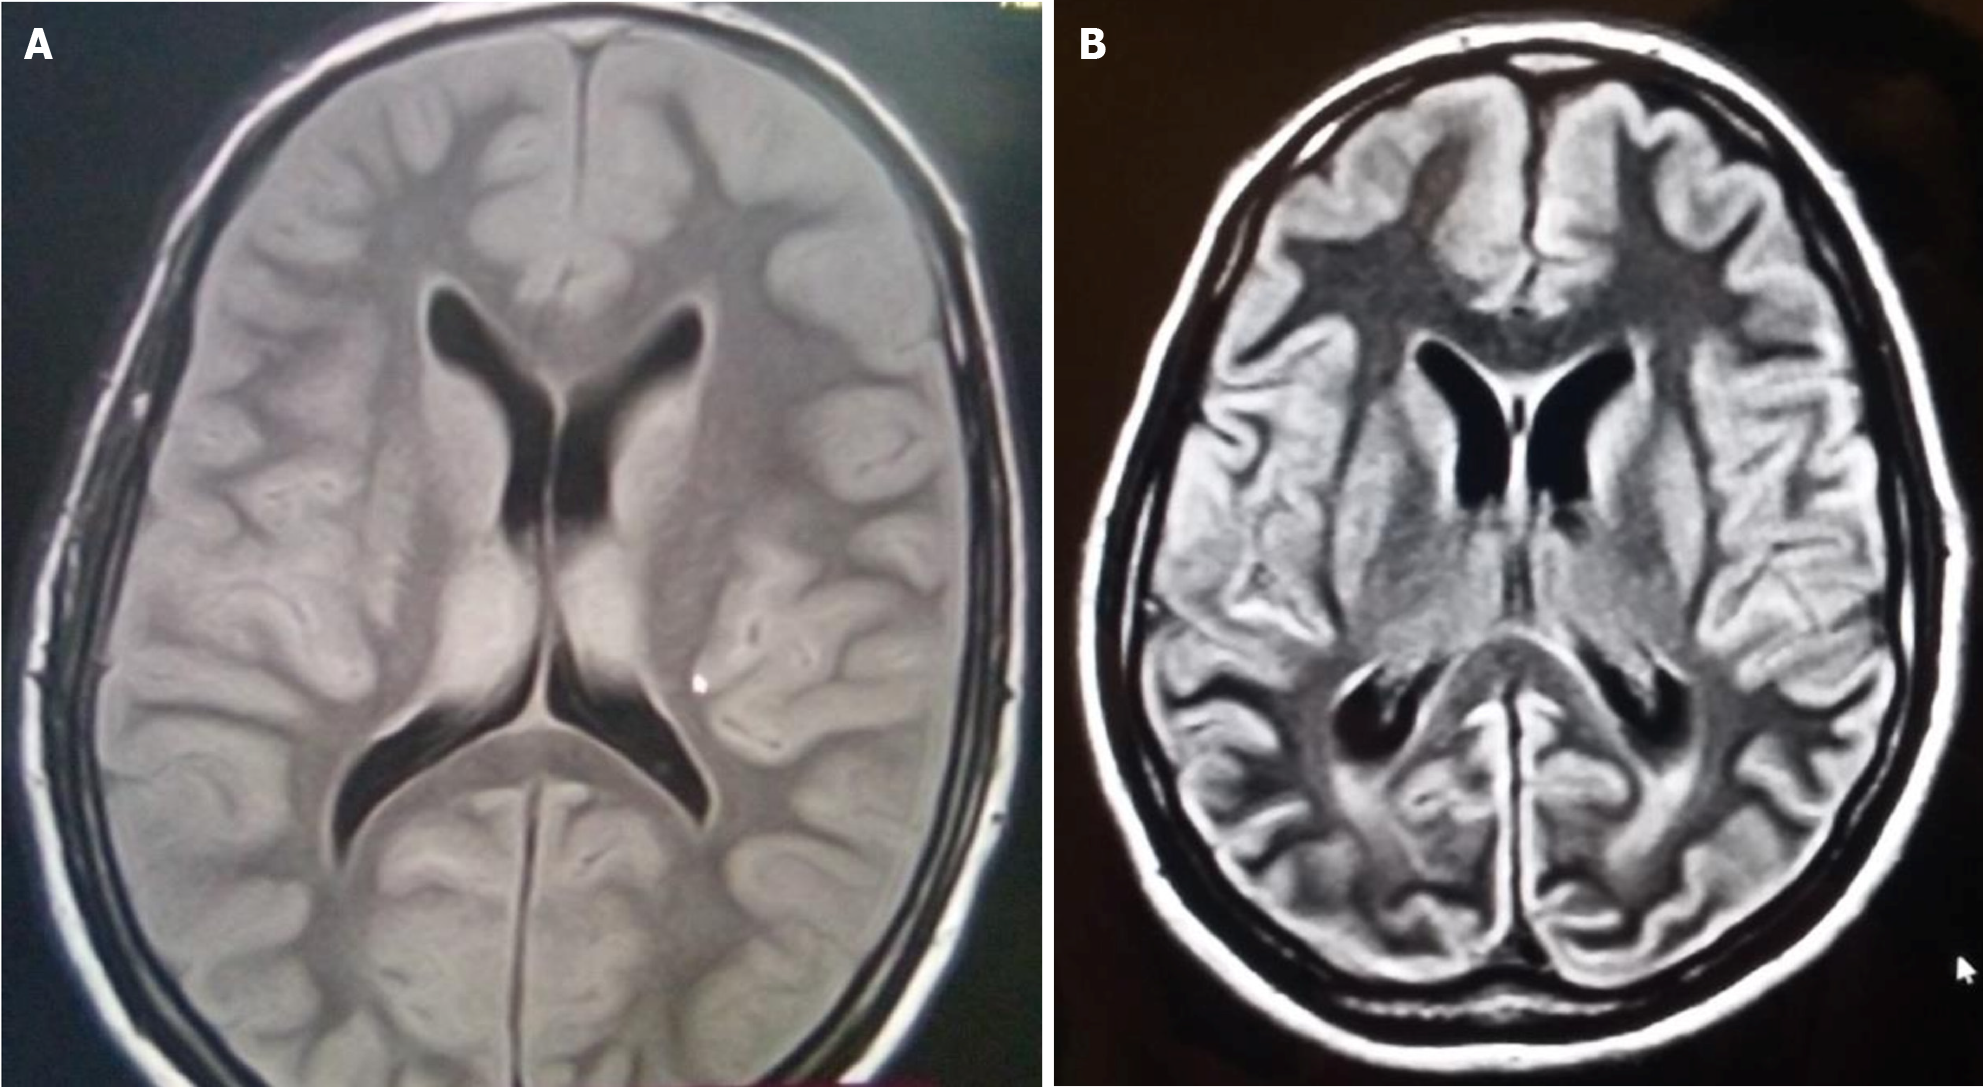

Fluid attenuated inversion recovery (FLAIR) sequence of magnetic resonance imaging (MRI) shows hyperintensities involving the basal ganglia, cortex and white matter (Figure 3A). Diffusion-weighted (DW) imaging, shows areas of restricted diffusion (Figure 4). Diffusion-weighted imaging (DWI) requires absolute diffusion coefficient map confirmation to avoid T2 shine-through artifacts. Watershed infarcts also may be seen[23]. The presence of multilobar alterations on DWI MRI images correlate with poor outcome[24]. The optimal window period for DWI is 24–72 hours, because it may report false-negatives in the hyperacute stage. In the subacute phase, the DWI hyperintensities decrease, and extensive FLAIR hyperintensities can be seen in deep grey matter[21]. In the chronic phase (>3 weeks), diffuse atrophy (Figure 3B), cortical laminar necrosis, and hydrocephalus may be seen[21-25]. Cortical laminar necrosis appears as gyriform hyperintensity in T1-weighted imaging[22]. Hydrocephalus is rare in pure HIBI. It may be seen in cases of comorbid intraventricular hemorrhage or trauma.

Figure 3

Figure 3 Magnetic resonance imaging. A: A patient with hypoxic-ischemic brain injury showing fluid attenuated inversion recovery hyperintensities in basal ganglia; B: A patient with chronic hypoxic-ischemic brain injury showing diffuse atrophy.